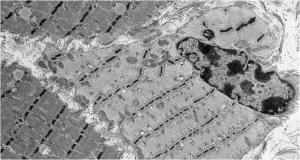

The second histological subtype is thick filament myopathy. There is selective proteolysis of myosin filaments, as seen by smudging of fibres on Gomorri Trichrome light microscopy and directly on electron microscopy. Since myosin carries the ATPase moiety, this is apparent on light microscopy as a specific lack of ATPase staining of both type I and type II fibres. Clinically, patients may have global flaccid paralysis, sometimes including ophthalmoplegia, and difficulty weaning from the ventilator. The CK may be normal or raised. Thick filament myopathy appears to have a similar pathophysiology to minimal change myopathy, but may be especially associated with high-dose steroid administration and neuromuscular blocking agents, particularly vecuronium.

Subtypes of Critical Illness Myopathy: Acute Necrotising Myopathy

This is a more aggressive myopathy, with prominent myonecrosis, vacuolization and phagocytosis. Weakness is widespread and the CK is generally raised. Its aetiology may relate to the catabolic state rendering the muscle susceptible to variety of additional, possibly iatrogenic, toxic factors. It may lie on a continuum with, and progress to, frank rhabdomyolysis.